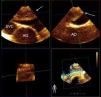

Mid-esophageal orthogonal views of the superior vena cava (SVC), ascending aorta (AO) and right pulmonary artery. Three-dimensional (3D) transesophageal echocardiography shows a large thrombus in the right pulmonary artery (white arrow), extending from the main pulmonary artery bifurcation. 3D reconstruction improves the morphological characterization of the thrombus.

A 40-year-old woman was admitted to the intensive care unit after extensive thoracic burns. During surgical debridement, she experienced rapidly progressive hypoxemia and hypotension requiring high-dose vasopressors, and oxygen saturation remained low despite 100% inspired oxygen concentration. Three-dimensional transesophageal echocardiography was performed, which showed a large thrombus in the right pulmonary artery, extending from the main pulmonary artery bifurcation (Figure 1). It also revealed right ventricular dilatation and severe tricuspid regurgitation (Figure 2A). Given the high bleeding risk associated with recent surgery, a decision was made to perform percutaneous thrombectomy with low-dose intra-arterial fibrinolysis instead of systemic full-dose thrombolysis. Pre-intervention angiography demonstrated a large filling defect in the right pulmonary artery with impaired distal flow (Figure 3A). Abundant thrombotic material was obtained (Figure 3C) and significant improvement in pulmonary circulation was noted (Figure 3B). After the procedure, the patient experienced a dramatic improvement in hemodynamic and respiratory parameters, enabling discontinuation of vasopressors and the use of lower inspired oxygen concentration. Chest radiography demonstrated wedge-shaped pleural based opacities (the “Hampton's hump” sign, Figure 3D). Follow-up echocardiography performed 48 hours later showed resolution of right ventricular dilatation and tricuspid regurgitation (Figure 2B).